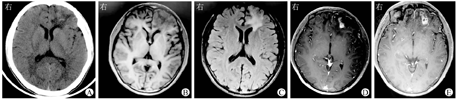

患者男,23岁,湖南省娄底市人,因"反复头痛3年余,加重10 d"于2021年10月25日收治复旦大学附属华山医院。患者2018年10月起无明显诱因下出现头痛,伴呕吐,非喷射性,呕吐物为胃内容物,无头晕、视物模糊,无腹痛、腹泻等不适,至外院予药物镇痛治疗,具体用药不详,后症状略有缓解。其间反复出现头痛,对症治疗后缓解。2021年10月15日患者无明显诱因再次出现头痛,至外院就诊,查血常规示:白细胞计数为10.45×109/L,中性粒细胞比例为0.768,CRP为0.44 mg/L。头颅CT检查提示:双侧额叶大片状异常密度灶,性质待定。给予甘露醇静脉滴注降颅压治疗后症状缓解,行头颅增强MRI检查提示:颅内占位性病变。为进一步诊治就诊于复旦大学附属华山医院感染科。否认高血压、糖尿病等慢性疾病史,否认肝炎、结核等传染病史,否认疫区流行病学史,否认食物、药物过敏史,否认吸烟史、饮酒史。患者体格检查未显示异常的神经系统体征。入院实验室检查示白细胞计数为6.02×109/L,血红蛋白为145 g/L,中性粒细胞百分比为0.476,嗜酸性粒细胞计数为0.35×109/L,嗜酸性粒细胞比例为0.056,血小板计数为257×109/L;血总IgE为77.28 μg/L;肝肾功能未见异常;ESR、CRP、铁蛋白、降钙素原等均未见异常。曲霉菌半乳甘露聚糖抗原试验(GM试验)阴性,β-D葡聚糖试验(G试验)为180.24 pg/mL。血清寄生虫抗体检测示:曼氏裂头蚴弱阳性。脑脊液蛋白质为388 mg/L,白细胞计数为2×106/L,糖为3.0 mmol/L,脑脊液培养阴性。脑脊液寄生虫抗体:阴性。脑脊液宏基因组学二代测序(metagenomic next-generation sequencing,mNGS)示曼氏迭宫绦虫,序列数为47。头颅CT检查提示两侧额部见不规则稍高及低密度混杂密度影,边界欠清,以左额部为著(图1A)。头颅MRI平扫检查示,双侧额叶见团片状异常信号影,平扫T1WI等低信号、T2WI及液体衰减反转恢复序列(fluid-attenuated inversion recovery,FLAIR)不均匀高信号,病灶边界不清,以左额叶为著;近旁脑回可见萎缩性改变(图1B、图1C)。头颅增强MRI检查示:病灶呈串珠样强化(图1D、图1E)。结合患者头颅MRI表现、血清免疫学结果、脑脊液mNGS结果,考虑临床诊断为脑裂头蚴病。患者于2021年11月9日全身麻醉下行"开颅病灶切除术",术中将左额极肉芽肿整块完整切除,灰黄色,质韧,边界清楚,血供不丰富,肉芽肿解剖未见活虫,可见长索状结构类似死虫体或肉芽隧道。术后病理示:(左额虫体窦道)(周围病灶)嗜酸性脓肿伴肉芽肿反应,局部坏死灶内见虫卵样结构,符合寄生虫感染。患者术后未服用抗寄生虫药物,术后6个月随访未出现不适症状主诉。

脑裂头蚴病的CT表现主要为脑实质内不规则形境界不清的低密度影,其内可见结节状或条带状等或稍高密度影,增强扫描后呈明显强化。脑裂头蚴病的MRI平扫检查示病灶常位于幕上、多发,灶周水肿带明显,但占位效应不重,有时灶周可出现负占位效应;增强扫描示病灶呈串珠样、匐行管状类似虫体形态的特异性强化,常见的典型表现包括隧道征、绳结征、串珠状或小环形强化灶等[1,2,3]。但在临床诊疗过程中由于影像学特异性并不十分明确,术前仅凭影像学表现确诊,存在较高难度,阳性率不高[5],陈宏等[6]报道的11例中仅1例术前明确为脑裂头蚴病。

本例患者以"头痛"起病,无明显的流行病学史,血常规提示白细胞及嗜酸性粒细胞均未见明显异常,脑脊液白细胞计数及蛋白质不高。头颅CT检查示两侧额部见不规则稍高及低密度混杂密度影,边界欠清。头颅MRI平扫检查见双侧额叶有团片状异常信号影,平扫T1WI等低信号、T2WI及FLAIR不均匀高信号,病灶边界不清,MRI增强见左侧额叶串珠样强化灶。血清寄生虫抗体弱阳性,但脑脊液寄生虫抗体为阴性。该患者脑脊液mNGS示存在曼氏迭宫绦虫,极大地帮助临床准确诊断该脑裂头蚴病患者。